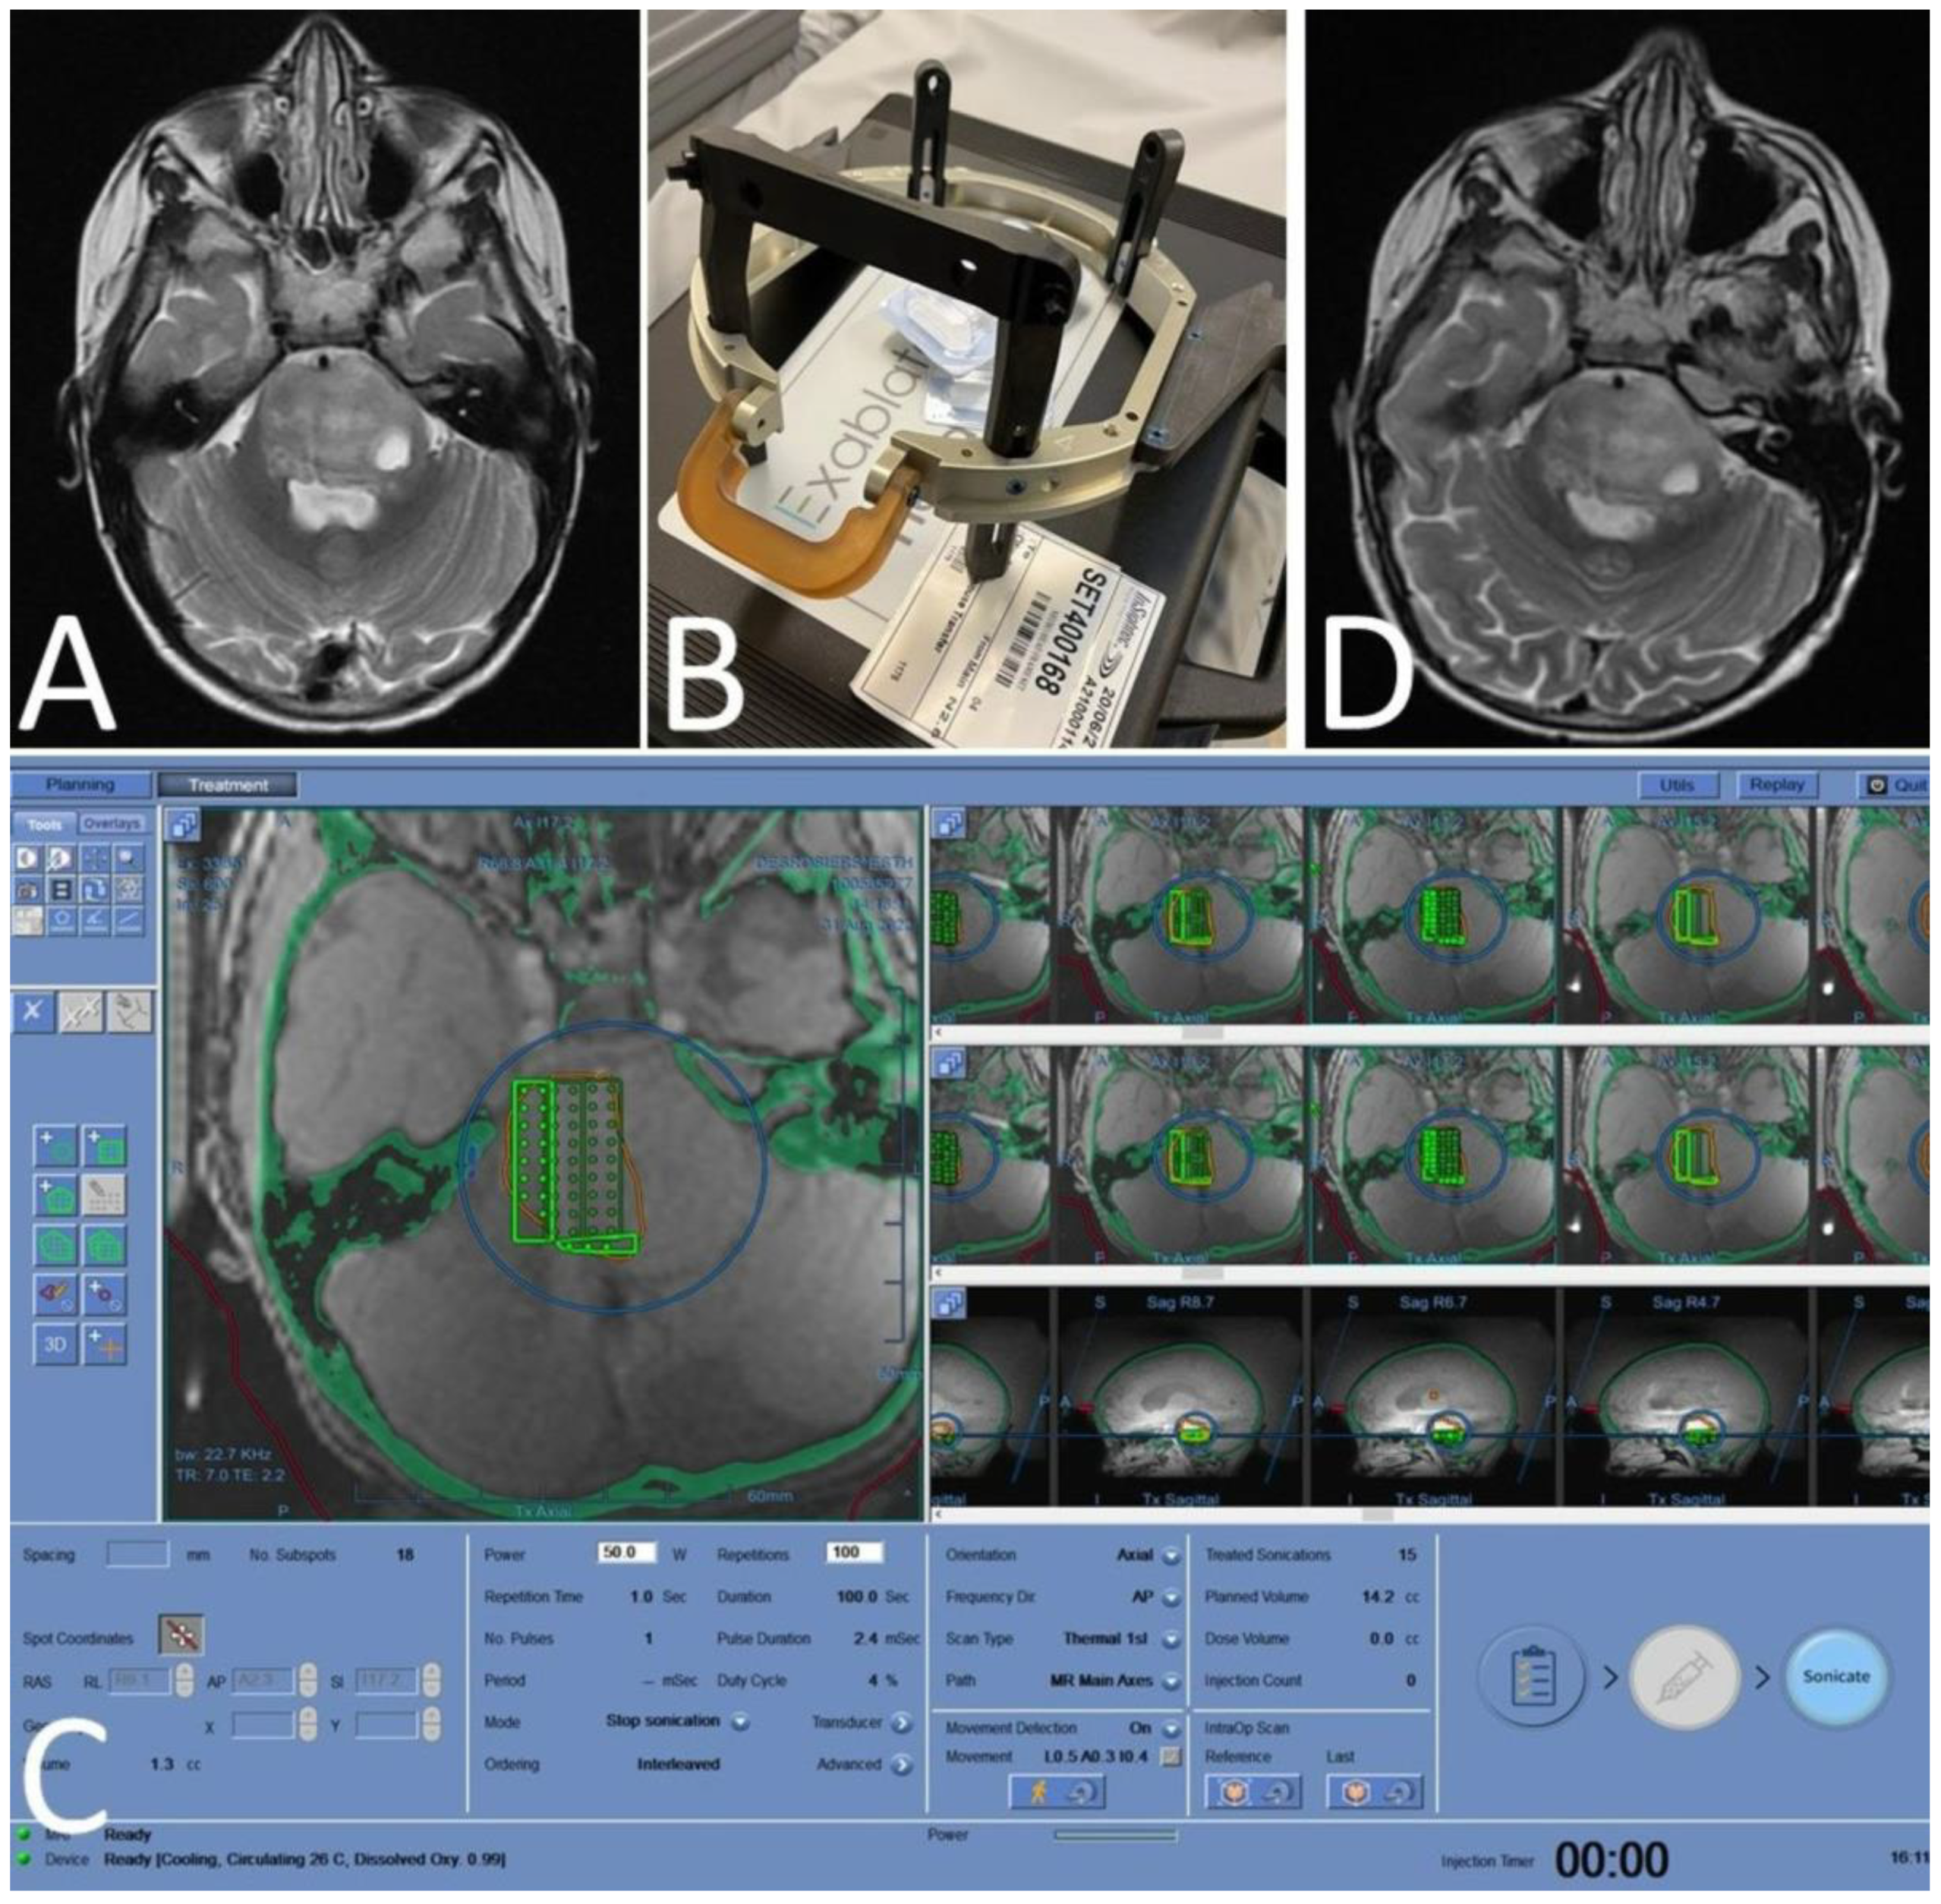

6.1.3. MRgFUS—Using ALA SDT as a Neurosurgical Tool

- Yoshida, M.; Kobayashi, H.; Terasaka, S.; Endo, S.; Yamaguchi, S.; Motegi, H.; Itay, R.; Suzuki, S.; Brokman, O.; Shapira, Y.; et al. Sonodynamic Therapy for Malignant Glioma Using 220-kHz Transcranial Magnetic Resonance Imaging-Guided Focused Ultrasound and 5-Aminolevulinic acid. Ultrasound Med. Biol. 2019, 45, 526–538. [Google Scholar] [CrossRef]

- Wu, S.-K.; Santos, M.A.; Marcus, S.L.; Hynynen, K. MR-guided Focused Ultrasound Facilitates Sonodynamic Therapy with 5-Aminolevulinic Acid in a Rat Glioma Model. Sci. Rep. 2019, 9, 10465. [Google Scholar] [CrossRef]

| NCT04845919 | Sonodynamic Therapy with ExAblate System in GBM Patients (Sonic ALA) | GBM | Phase 2, single center | Single treatment of oral 5-ALA with MRgFUS (Exablate), followed by surgery 15–21 days post SDT | Safety, biomarker analysis |

| NCT04559685 | Study of Sonodynamic Therapy in Participants with Recurrent HGG | HGG | Phase 0, single center | Single treatment of IV ALA (SONALA-001) with MRgFUS (Exablate), followed by surgery 4–6 days post SDT | Safety, biomarker analysis, immune profiling |

| NCT05370508 | A Study of Sonodynamic Therapy Using SONALA-001 and Exablate 4000 Type 2.0 in Subjects with Recurrent GBM | rGBM | Phase 1/2, multicenter | Monthly treatments of IV ALA (SONALA-001) with MRgFUS (Exablate) device | Safety and tolerability, determination of MTD and RP2D |